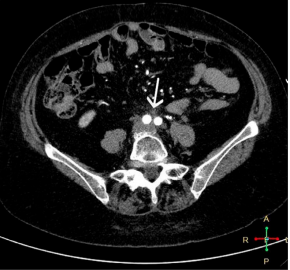

MDCT with contrast was performed, which reported a slight decrease in the retroperitoneal image (Figure 1 and 2), so it was decided to continue with corticosteroid treatment and outpatient follow-up to schedule surgery with biopsy.

Figure 2 MDCT with intravenous contrast, excretory phase, axial view. There is soft tissue dense formation encompassing both ureters.